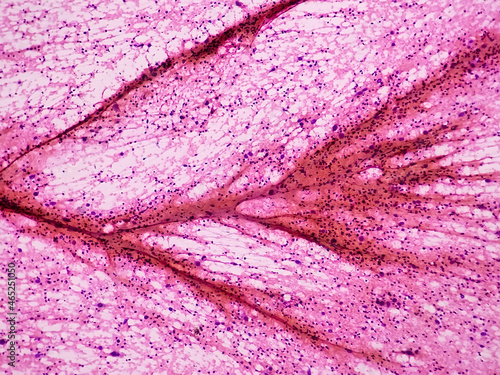

Mikrofotografi - Plakater, Poster, Billeder på lærred